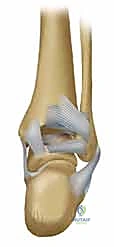

المرحلة الثالثة: رد العظام وتثبيت الكعب الوحشي (الشظية)

يبدأ الجراح عادة بإصلاح الشظية لأنها تعتبر "العمود الفقري" لاستقرار الكاحل. يتم إرجاع قطع العظم إلى مكانها التشريحي الطبيعي (الرد المفتوح). ثم يتم تثبيتها باستخدام شريحة معدنية (Plate) ومجموعة من المسامير (Screws) لتثبيتها بقوة.

المرحلة الرابعة: تثبيت الكعب الإنسي (الظنبوب)

بعد استقرار الجانب الخارجي، ينتقل الجراح للجانب الداخلي. يتم تنظيف منطقة الكسر من أي أنسجة محشورة، ثم يتم رد الكعب الإنسي وتثبيته غالباً باستخدام مسمارين طويلين (Cancellous screws) أو تقنية الأسلاك والشد (Tension band wiring) حسب شكل الكسر.